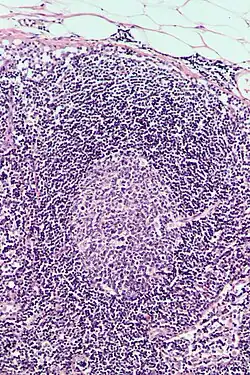

| Image | Name | Subtype | Class | Alternate names | Diameter (μm) | Main targets | References |

|---|---|---|---|---|---|---|---|